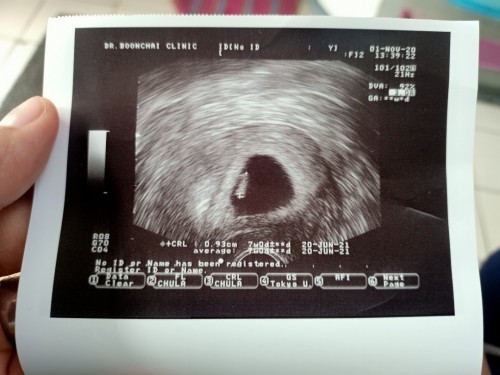

7 Week มีภาวะแท้งคุกคาม

2 วันที่แล้วมีเลือดสีน้ำตาลออกมา ปนๆ กับเลือด วันนี้ร้อนใจไปหาหมอ อย่างน้อยก็เจอตัวเล็ก แล้วก็หัวใจยังเต้น ฉีดยากันแท้งไป1 เข็ม เฮ้ออออ 😢